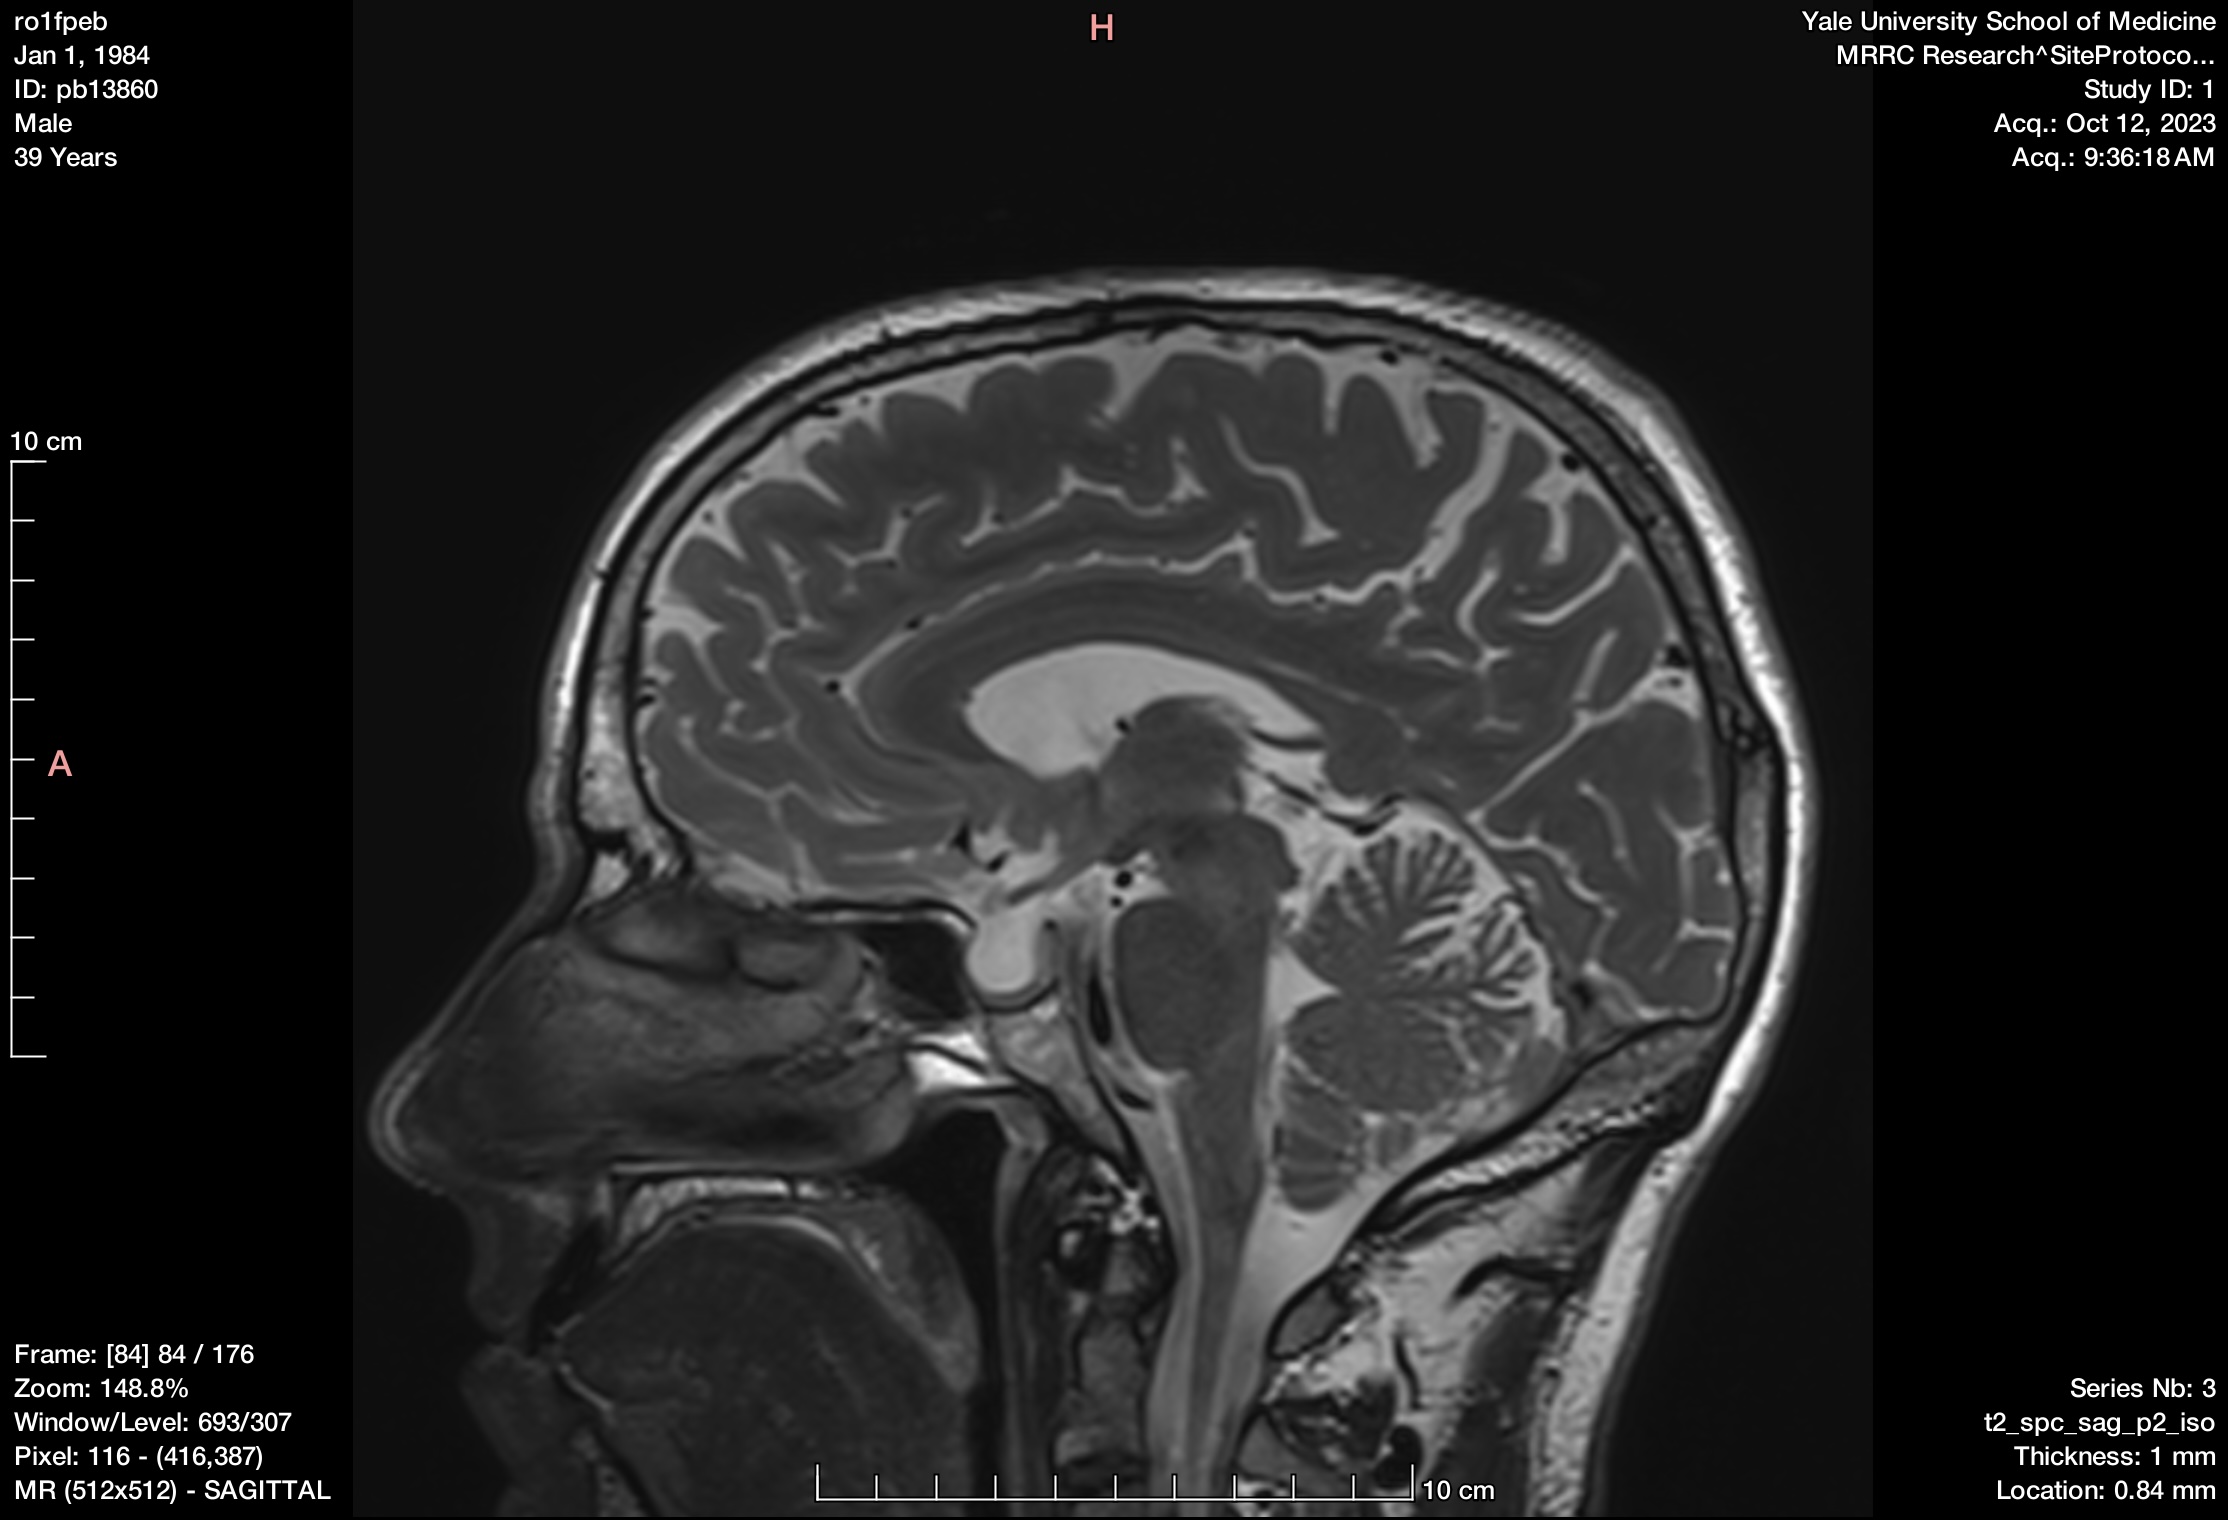

I recently was able to be a participant in one of the newer bipolar research studies going on. I got lots of cool data like the image below, and it only required time, many blood draws, and my first arterial line!

A still from a scan of my brain. Somewhere in there lies the problem...I think. In late 2023 I participated in a research study and for the first time got scanned with MRI, fMRI, MRS, PET, and EEG machines.